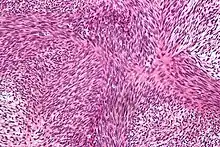

| Micrograph of a tumour with the herringbone pattern as may be seen in fibrosarcoma. H&E stain. | |

The tumor may present different degrees of differentiation: low grade (differentiated), intermediate malignancy and high malignancy (anaplastic). Depending on this differentiation, tumour cells may resemble mature fibroblasts (spindle-shaped), secreting collagen, with rare mitoses. These cells are arranged in short fascicles which split and merge, giving the appearance of "fish bone" known as a herringbone pattern. Poorly differentiated tumors consist in more atypical cells, pleomorphic, giant cells, multinucleated, numerous atypical mitoses and reduced collagen production. Presence of immature blood vessels (sarcomatous vessels lacking endothelial cells) favors the bloodstream metastasizing. There are many tumors in the differential diagnosis, including spindle cell melanoma, spindle cell squamous cell carcinoma, synovial sarcoma, leiomyosarcoma, malignant peripheral nerve sheath tumor and biphenotypic sinonasal sarcoma.